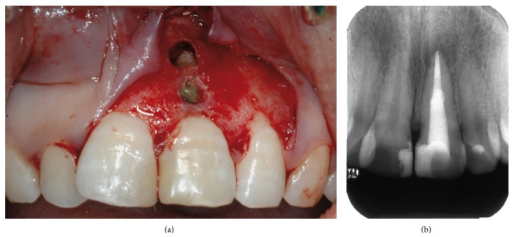

El curetaje es un tratamiento de eliminación de la placa bacteriana que va más allá de la simple limpieza de la superficie de los dientes y que se realiza cuando existe inflamación de las encías por una enfermedad periodontal (gingivitis o periodontitis).

El objetivo del curetaje es precisamente eliminar las bacterias de la bolsa periodontal, raspando las raíces** del diente y eliminar el sarro acumulado, mediante la utilización de un instrumento llamado cureta.

(root) The debridement and planning to smoothness of the root surface of a tooth to eliminate deposits on the root.

(subgingival) The process of debridement* of the epithelial attachment, the ulcerated and entire (pocket) epithelium, and subjacent inflamed and altered gingival tissues. The procedure is no longer recommended for the health of the periodontium.

An additional procedure called curettage has been also included in nonsurgical periodontal therapy and it includes the process of debriding the soft tissue wall of a periodontal pocket.